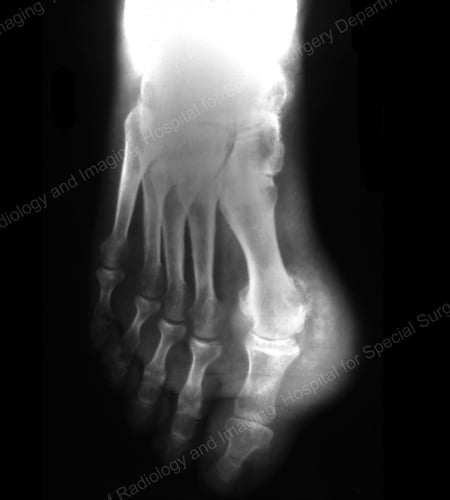

X-rays are the standard imaging technique for gout (See Figures 12-17: Figure 12: Gout of the Base of the 1st Toe; Figure 13: Gout of the Distal Finger Joints; Figure 14: Gouty Change and Soft Tissue Calcification About the Base of the 1st Toe; Figure 15: Gouty Destruction at Multiple Finger Joints; Figure 16: Gouty Erosion at the Proximal Ulna at the Elbow; Figure 17: Large Tophus Seen as Soft Tissue Mass at the Elbow) but in special cases, such as when gout needs to be separated from infection or tumor, magnetic resonance imaging (MRI) (Figure 18: MRI of the Knee Showing Gouty Soft Tissue Mass and Erosion of the Kneecap) or ultrasound (Figure 19: Power Doppler Study Showing Gouty Inflammation at the Base of the 1st Toe) will be helpful. A newer technique called a dual-energy CT scan (DECT) can show urate crystals in green color.

X-ray of gout at the base of the 1st toe

Figure 12: Gout of the Base of the 1st Toe

X-ray of gouty change and soft tissue calcification about the base of the 1st toe

Figure 14: Gouty Change and Soft Tissue Calcification about the Base of the 1st Toe